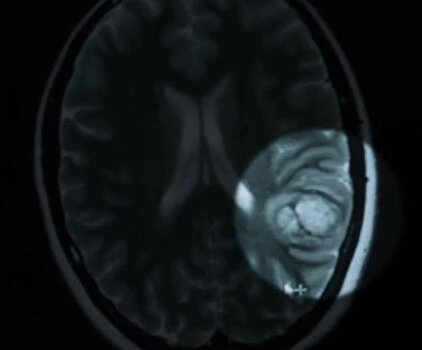

Fakat, Schardt beyninde kavernom adı verilen, yanlış biçimlendirilmiş kan damarlarının dolaşmasından kaynaklanan bir nöbet geçiriyordu.

Bu kavernom ise dil merkezine oldukça yakındı. Doktorlar ameliyat sırasında beyninin belli noktalarına baskı uygulayacaktı ama Schardt'in konuşma yetisini kaybetmekten korkuyorlardı.